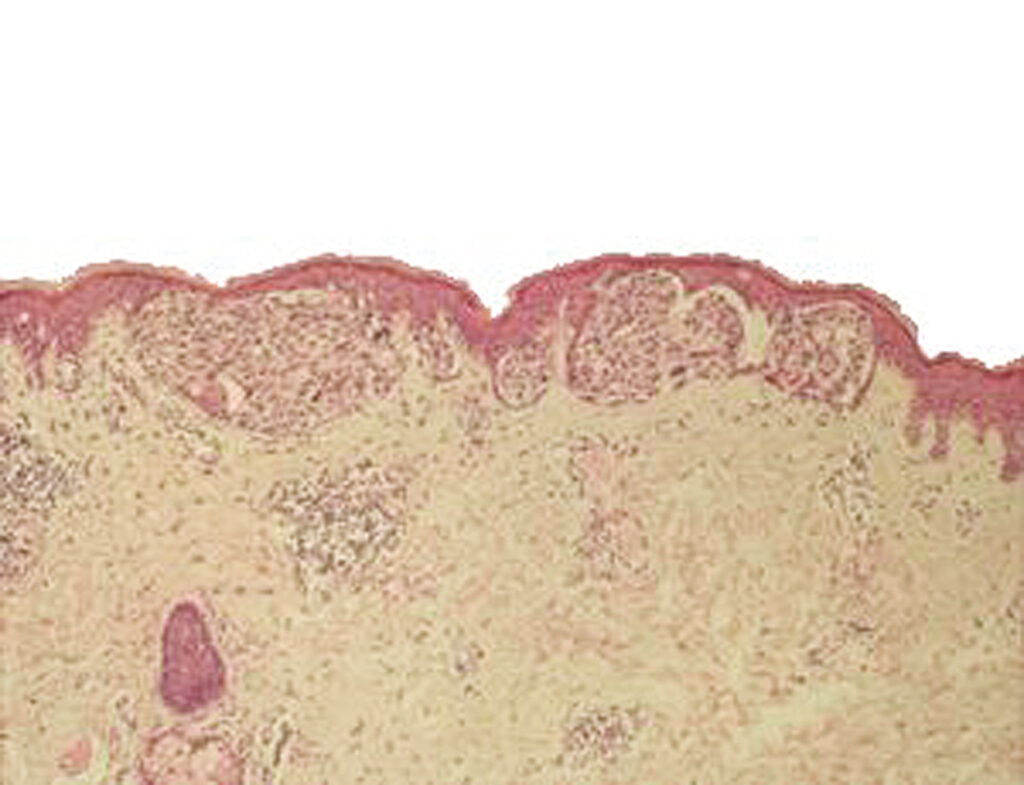

When the piece of skin is removed it is sent to a pathology lab where it is processed. This processing takes time. It involves placing the skin in melted wax to form a so-called block. When the wax cools it hardens and the block is therefore firm enough to be handled. The block is placed in a machine, which allows a skilled technician to slice the tissue thinly and place the tissue (called a section shown below) on glass slides.

Stain is then added to the slides so that the nature (type) of the tissue becomes clear to the pathologist. The pathologist is a doctor who then looks at the slide, and interprets the pattern he or she sees and makes the diagnosis.

This is a melanoma that is at a very early stage of development. The cancer cells are entirely in the top layer of the skin (the epidermis).

This type of melanoma is entirely curable and should never come back. The diagram shows the appearance of an in situ melanoma; the cancer cells are shown in black.

Examples of melanoma in situ

Radial growth phase melanoma

This is a melanoma that has started to grow but still mainly sideways in the skin rather than downwards into deeper layers. The most common type of melanoma is known as a superficial spreading melanoma, and early superficial spreading melanomas are in radial growth phase. These melanomas typically have an irregular shape and a variable or mixed colour.

The diagram below shows the appearance of a radial growth phase melanoma. The cancer cells are shown in black.

People with this type of melanoma should be cured by surgery. The melanoma is unlikely to come back after it has been removed.

Examples of radial growth phase melanomas

Vertical growth phase melanoma

This is a melanoma that has started to grow downwards into the skin. Again the diagram below shows the cancer cells in black. This is a potentially more serious type of melanoma.

The likelihood of it coming back or having spread to other parts of the body varies and depends on how deeply within the skin it has grown.

This depth is known as the Breslow thickness. Vertical growth phase melanomas may develop from radial growth phase melanomas.

Examples of vertical growth phase melanomas